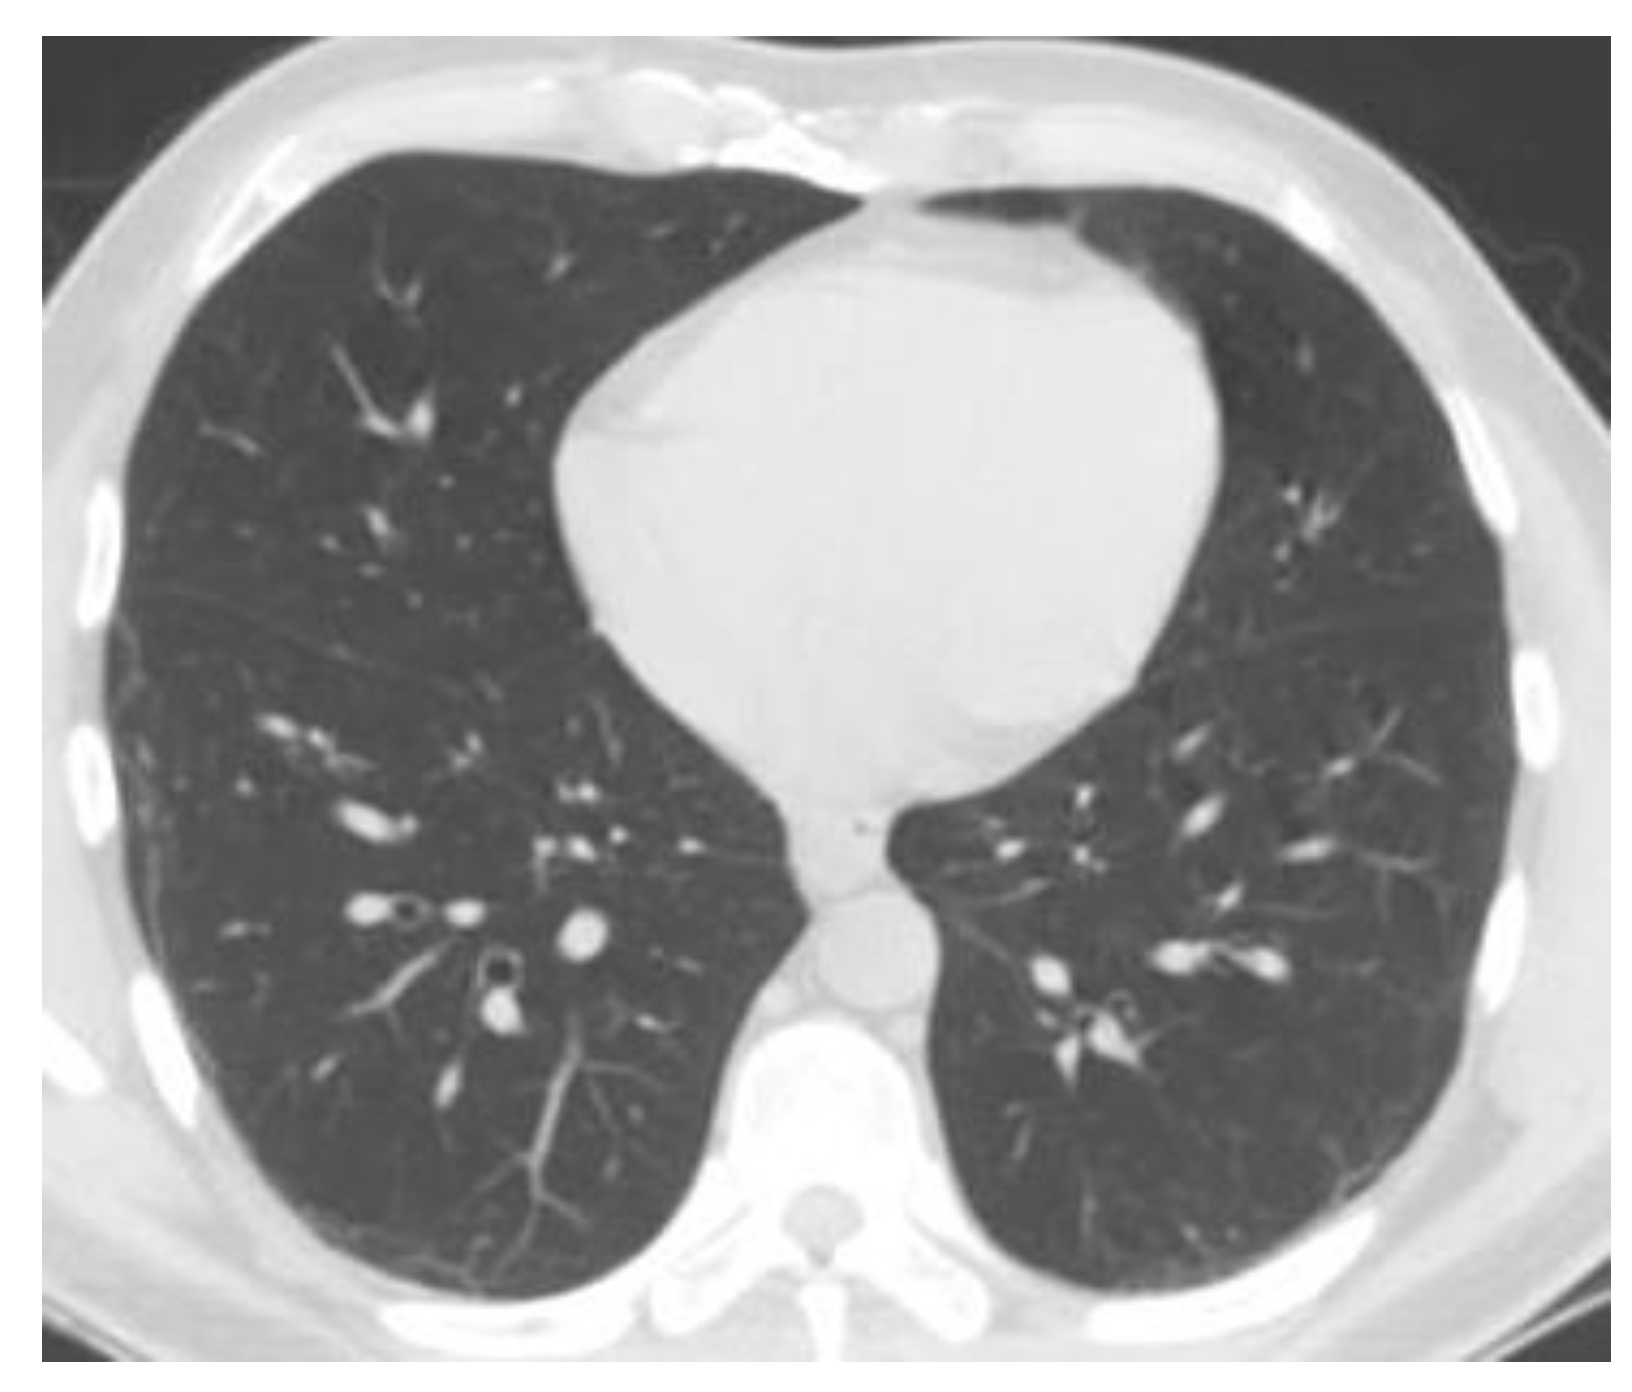

Figure 9 and Figure 10 show the original CT lung image, respectively, and the defined mask for the COVID-19 lung CT image, framed in a blue border in Figure 10.

Figure 9. Original COVID-19 lung image.